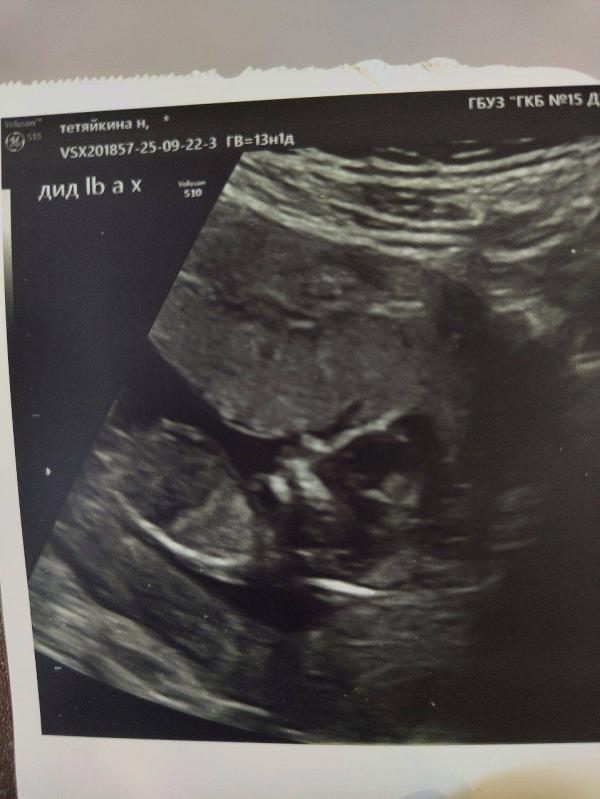

Прошли 1 скрининг с моей принцессой 🥰🌺 Второй раз узнаю пол в 11 недель и на скрининге его подтверждают😅

Срок 13,1нед, ктр 75мм, прикрепление по передней, плацента доходит до зева( проходили, ждём когда поднимется 🙏), шейка 33мм, отслойка рассосалась 🎉💥сама, без коричневых выделений, просто нужно было время🙂↕️